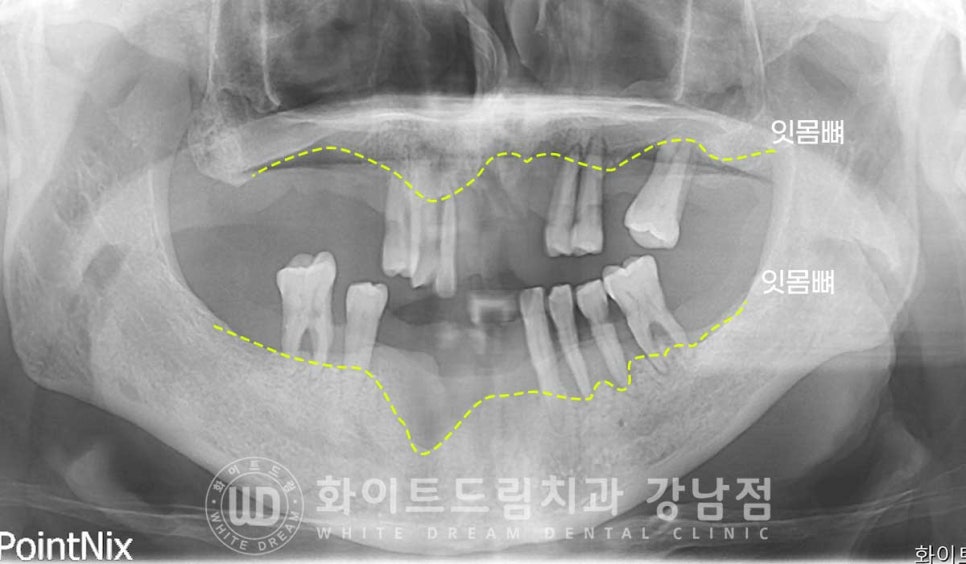

x-ray를 보면 잇몸뼈의 상태가 적나라하게 보이는데요.

하악 앞니 쪽은 잇몸뼈가 폭탄을 맞은 것처럼 큰 구덩이가 패어있는 상태이고

상악 어금니 양쪽은 잇몸뼈가 거의 남아있지 않은 상태입니다.

그나마 다행인 것은 부분적으로 크게 무너진 상태여서

임플란트 식립이 가능한 상태였답니다.